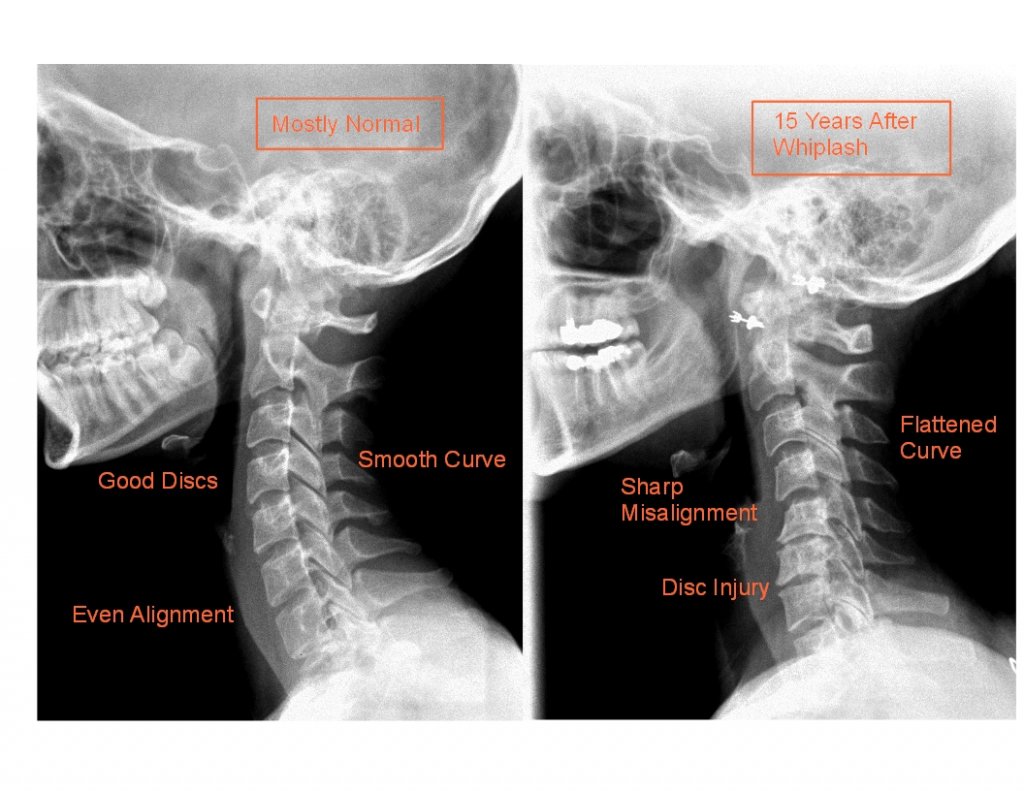

Wśród czynników urazowych dominują urazy komunikacyjne, ze szczególnym uwzględnieniem urazu typu Wiplash Injury (cervical acceleration–deceleration injury CADI czyli uraz „smagnięcia biczem „ stanowiący najczęstszy i często nieleczony typ urazu kręgosłupa szyjnego. Uraz tego typu powstaje w mechanizmie deceleracyjno-akceleracyjnym czyli wiąże się ze zmianą przyspieszenia , najczęściej dochodzi do niego w konsekwencji zderzenia pojazdów powodującego gwałtowne odrzucenie głowy w tył a następnie równie szybkie zgięcie jej do przodu ( sekwencja ta jest typowa dla uczestnika wypadku komunikacyjnego przy uderzeniu od tyłu, w przypadku zderzenia czołowego zmienia się sekwencja ruchu natomiast uraz tkanek pozostaje ). W urazie Wiplash największa kumulacja traumatyzacji występuje w segmencie C5-C6 prowadząc do przekroczenia fizjologicznej ruchomości. W zależności od siły i mechanizmu urazu uszkodzeniu ulegają struktury więzadłowe, mięśnie, kości , torebki stawowe, krążki międzykręgowe oraz rdzeń kręgowy i nerwy. Podobny urazowy charakter wykazuje rownież uprawianie niektórych sportów np. sporty walki, skoki na bungee, roller coaster czy na skutek kopnięcia lub wstrząsania z niekontrolowanym ruchem głowy ( zespół potrząsanego dziecka )

Odwlekanie podjęcia prawidłowego leczenia może prowadzić do trwałych , groźnych dla zdrowia skutków , zobrazowanych na zdjęciu poniżej